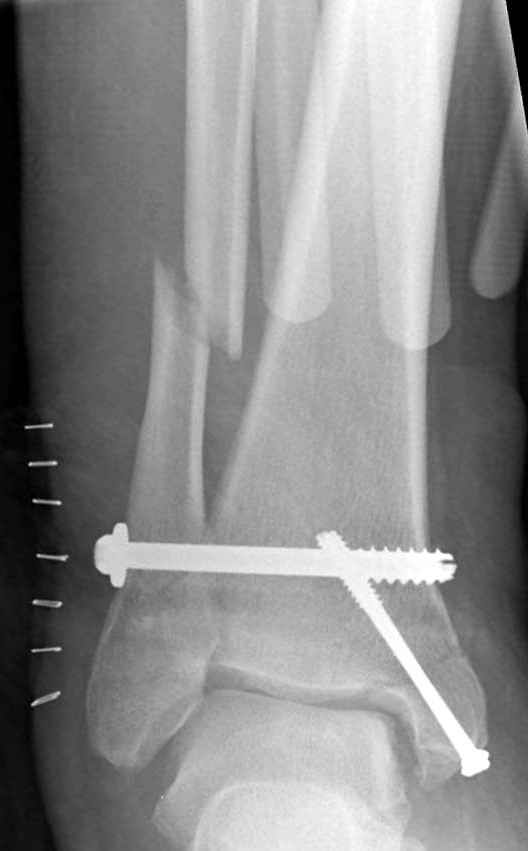

Если до сих ничего не сделано, с артродезом сустава в данный момент я бы повременил, на выставленных январских снимках хорошо сохранившийся сустав, а в "мортиз" (трехчетвертной) и на боковых снимках не менее 5 мм укорочение малоберцовой кости. Косые переломы лучше фиксировать пластинами, как то мы разбирали случай, где было отмечено, что это закон "таранная кость всегда следует за малоберцовой".

В данном случаи я бы уговорил больного на реконструкцию, для этого после удаления шурупов, спереди очистить от рубцов синдесмоз, несросшуюся наружную лодыжку - остеотомия по линии перелома и компрессирующий (lagging technique) кортикальный шуруп 3.5 мм по поперечнику остеотомии. Следующий этап - восстановление длины малоберцовой за счет удлинения, сделать поперечную остеотомию где-то на уровне сантиметр выше вашего синдесмозного шурупа, наложить длинную пластинку, прикрепить пластину за дистальный конец двумя или тремя шурупами; сохраняя контакт пластины с костью, имеющимся

compression&tension device AO system (при отсутствии любой lamina spreader подойдет, создать дистанцию между пластиной и шурупом, проведенным проксимальнее пластины) толкая проксимальный отдел пластины, низвести пластину, мортиз рентгенограмма подскажет на сколько. Если заранее сделать предоперационный план (ренгенограмма другой стороны), тогда точно можно определить, на сколько вам необходимо сделать поперечную остеотомию малоберцовой кости, для закрытия создавшегося дефекта.

Убедившись, что желаемая длина восстановлена, окончательная фиксация пластины, при этом через пластину пару 3.5 мм шурупов на синдесмоз, предпочтительно в четыре кортекса и оставить на 3 мм длиннее, если под нагрузкой синдесмотический шуруп сломается, сломанный конец легче удалить с медиальной стороны.

Медиальная сторона не в нагрузочной зоне, и там большая дыра - если есть 2.7 мм шурупы, или пару спиц в ваших условиях или методика Лазарева. Необходимо уделить внимание к мягким тканям, обнажается кость с латеральной стороны и у места где проводится остеотомия.

После 5-6 недели после травмы сделана повторная операция, обошлись без удлинения малоберцовой.